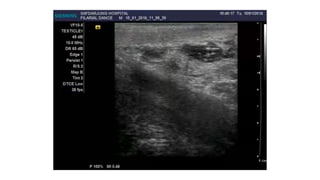

Ultrasonography High frequency ultrasonography (USG) of scrotum and

female breast coupled with Doppler imaging may result in identification of motile

adult worm (filaria dance sign) within the dilated lymphatics.

 Adult worm may be visualized in the lymphatics of the spermatic cord in up to

80% of the infected men with microfilaria associated with W. bancrofti.